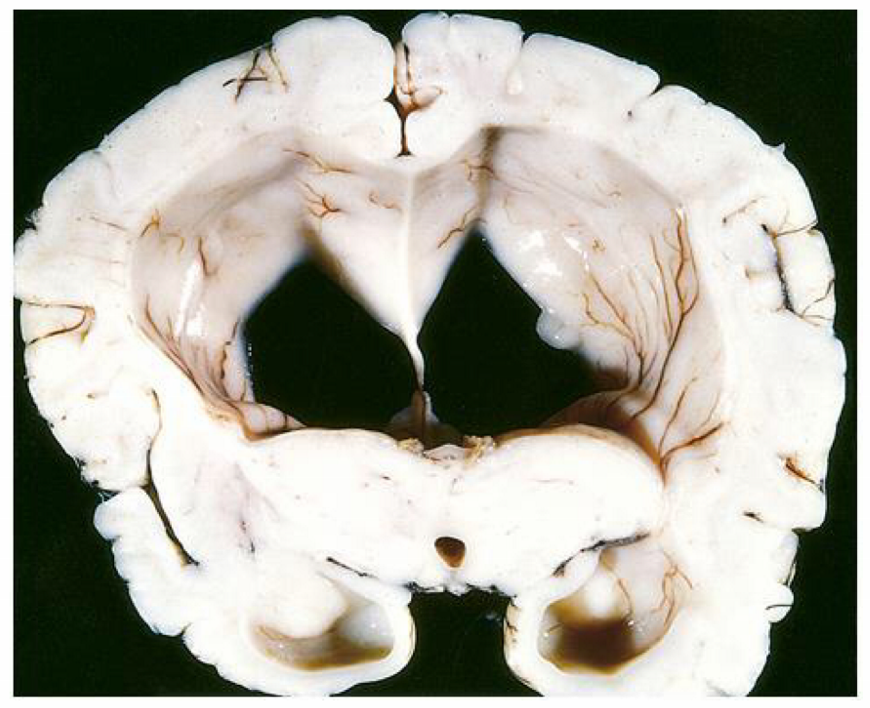

in the communicating form of the condition seen in the image, there is dilation of ___

in the communicating form of the condition seen in the image, there is dilation of ALL ventricles

the communicating form of the condition seen in the image can due to scarring/fibrosis of ____ or ____

the communicating form of the condition seen in the image can due to scarring or fibrosis of the arachnoid villi d/t tumors or infxns (TB, meningitis) or subarachnoid hemorrhage

the communicating form of the condition seen in the image is caused by reduced ____, such as in ____

the communicating form of the condition seen in the image is caused by reduced CSF resorption, such as in arachnoid fibrosis

the normal pressure form of the condition seen in the image is characterized by the triad of:

wet = urinary incontinence

wobbly = ataxia

the ex vacuo form of the condition seen in the image causes dilation of ____ due to ____ and causes a compensatory ____

the ex vacuo form of the condition seen in the image causes dilation of all ventricles due to cerebral atrophy and causes a compensatory increase in CSF

the non-communicating form of the condition seen in the image occurs between ____ & ____ or between ____ & _____

the non-communicating form of the condition seen in the image occurs between lateral & 3rd ventricle or between 3rd & 4th ventricle